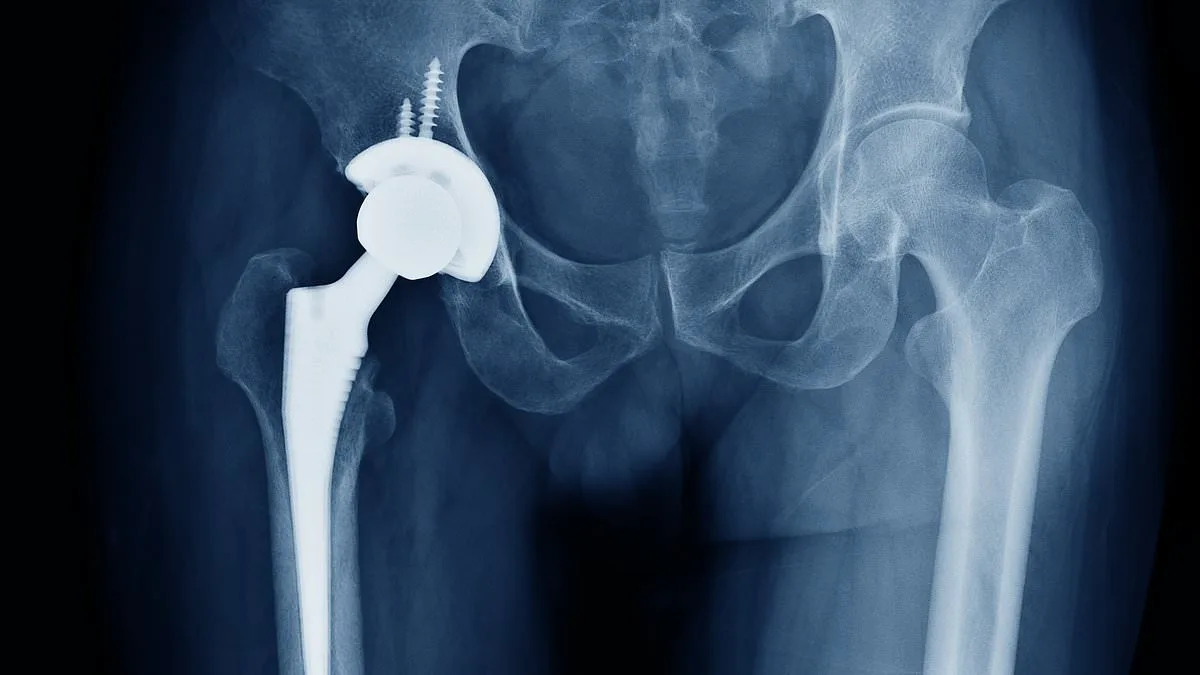

NHS Crisis: Bone Cement Shortage Halts Thousands of Hip and Knee Replacements